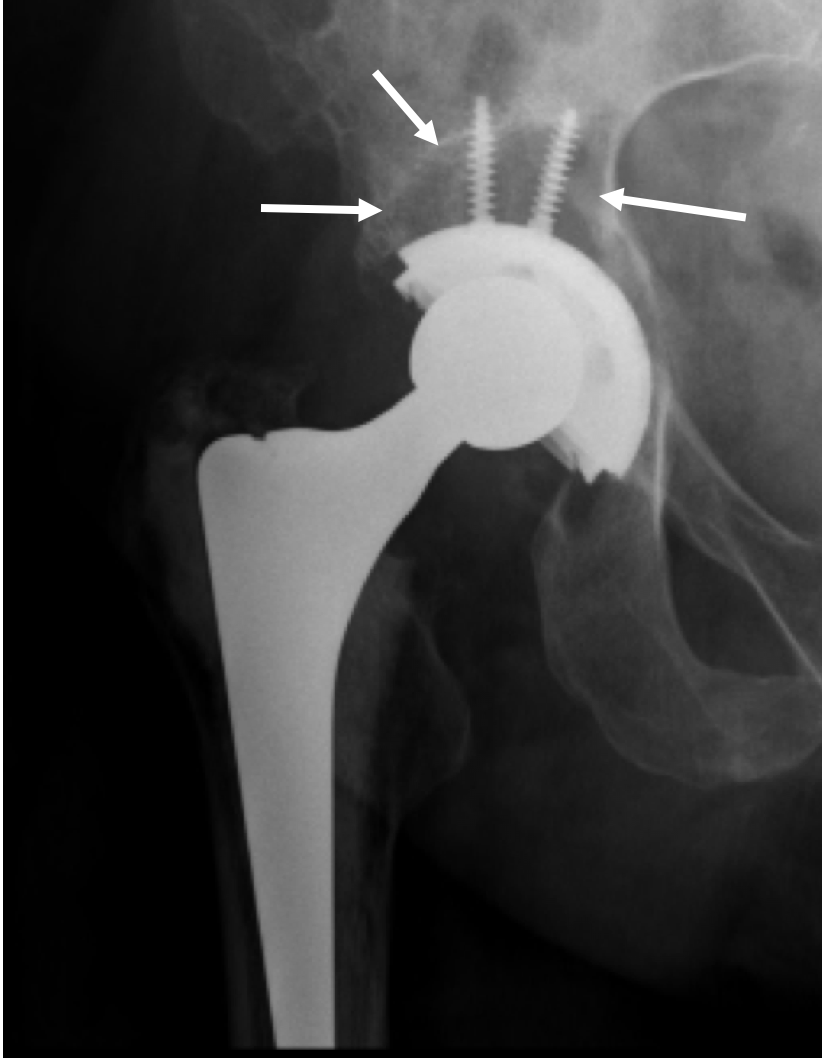

What Is Revision Hip Replacement? HipReplacement totalhipreplacement How Painful Is Hip Replacement Recovery what’s a typical hip replacement recovery timeline? This can vary depending on your age and general health. learn what to expect after hip replacement surgery, from the hospital stay to the recovery milestones. How much pain will you be in? complete recovery from a hip replacement surgery is a long process, taking several months to a year.. How Painful Is Hip Replacement Recovery.